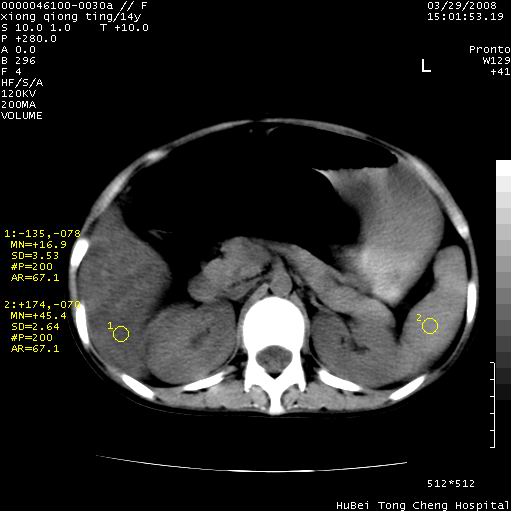

中下腹及盆腔ct轴位平扫+增强扫描(层厚10mm,螺距1.0,重建间隔10mm),图像如下:

(注:患儿检查当日上午9时口服胃肠道对比剂,下午3时许行ct扫描检查,未行对比剂直肠保留灌肠,检查当日患儿腹泻)

中下腹及盆腔ct轴位扫描(ps+ce)提示:腹部肠管明显充气扩张,并见数个不同宽度之气液平面;疑不全性肠梗阻或肠郁张。临床会诊考虑为患儿腹泻,肠郁张所致;后来未经特殊处理,患儿大便恢复正常,亦无腹胀。

临床出院诊断:1)结核性腹膜炎。2)腹膜后淋巴结结核。3)脂肪肝。